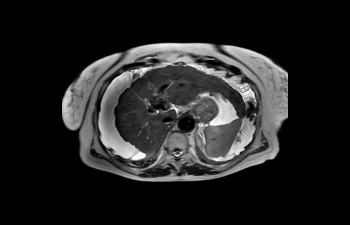

Liver image

Liver with ascites